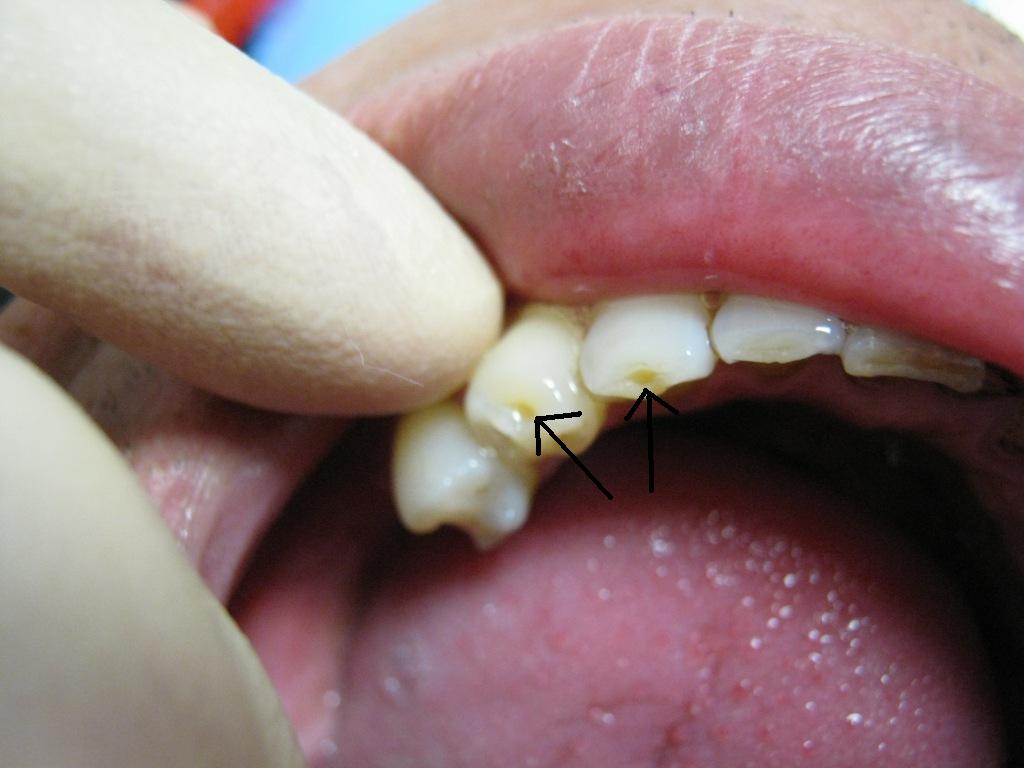

00f72645.JPG更に、歯の先端がこのように窪む人が多い

これは主に前歯部で見られるような気がする

これってなんか名前あったっけ?つけられててもいいような気がするんだが

まだないなら学会に発表して私の名前つけてもらおうか・・・無理っぽいが